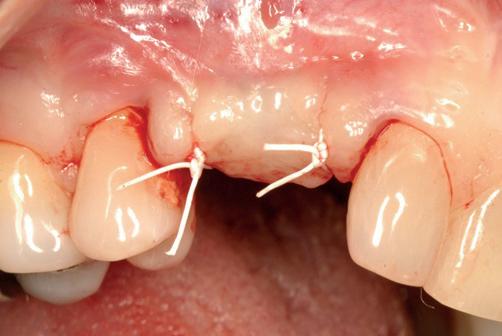

Implantologische behandelingen in het esthetische front vragen meer dan technische vaardigheid alleen. Ze vragen om overzicht, timing, vertrouwen en een team dat als vanzelf samenwerkt onder druk. Juist bij complexe casussen, waarin angst, infectie en hoge esthetische verwachtingen samenkomen, wordt zichtbaar hoe bepalend de rol van de tandartsassistent is.

Deze casus beschrijft een uitgebreide immediate implantaatbehandeling bij een patiënt die door meerdere collega’s werd geweigerd. Niet omdat de mogelijkheden ontbraken, maar omdat de complexiteit vroeg om een perfect afgestemde samenwerking. Het verhaal laat zien hoe de assistent in zo’n traject veel meer is dan een uitvoerende kracht of “mal”, maar een dynamische surgical guide die het proces mede stuurt, bewaakt en mogelijk maakt.De patiënt: wanneer alles samenkomt

Lateraal van de implantaten wordt de kaak fors uitgebouwd volgens de Hybride GBR-techniek met Oragraft (allograft) van Lifenet die wordt vermengd tot een cocktail met BioOss (xenograft) van Geistlich, autoloog geoogste botsnippers en verzameld bloed uit het wondgebied. De botgraft wordt bedekt met een Ossix (crossed linked) membraan en met Hyadent (hyaluronzuur) overspoten. De sinuslift wordt gelijktijdig met de laterale botopbouw volgens de Caldwell Luc methode uitgevoerd en de uitgeprepareerde holte opgevuld met de botgraft. De flaps worden eerst horizontaal ontlast (gemobiliseerd) en vervolgens naar elkaar toe gehecht met vicryl rapide. Daarbij wordt gebruikgemaakt van horizontale matrassen, zodat de wondranden passief tegen elkaar

komen te liggen en de flaps primair gesloten kunnen worden. Het passief sluiten van een flap voorkomt wonddehiscenties in de genezingsfase die als complicaties kunnen optreden en botregeneratie verstoren. Daarnaast wordt bij een wonddehiscentie het risico op infectie van de graft sterk verhoogd waardoor het gewenste resultaat niet kan worden bereikt. Afstoting van graft materiaal komt dan veelvuldig voor soms gecombineerd met abcesvorming als geen voorzorgsmaatregelen worden genomen. Complicaties moeten daarom nauwlettend gevolgd worden totdat ze verdwenen zijn. De patiënt krijgt na chirurgie postoperatieve instructies en adviezen over de postoperatieve zorg. Daarbij wordt ook de nadruk gelegd op het koelen (coldpack) en zijdelingse druk op de wang. Het blijkt dat koelen en het uitoefenen van druk op het operatiegebied oedeem en hematoomvorming grotendeels kunnen verminderen en soms zelfs kunnen voorkomen.